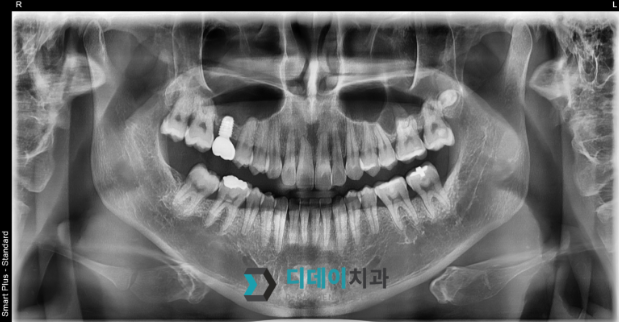

양쪽 위아래 어금니 치주염으로 내원하신 환자분입니다.

양쪽 어금니 심한 치주염으로 인해 발치 후

즉시 임플란트 식립 진행했습니다